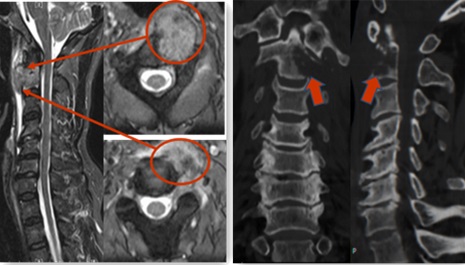

家人看他如此痛苦,于是带他到番禺区中医院住院治疗。经检查结合影像学报告,考虑为肝内胆管细胞癌伴寰枢椎骨转移。寰枢关节是高位脊髓及生命中枢所在处,肿瘤的位置决定着该手术的难度很高。“患者颈痛,走路不稳,是寰枢椎破坏导致的颈椎不稳和脊髓受压所致。” 脊柱外科大主任蔡东岭主任表示,影像学检查发现肿瘤破坏了颈2椎体的一半,开始向椎管内生长,如果不及时治疗,病情继续发展将导致手脚单侧或双侧麻木、手脚无力,严重时将导致瘫痪。

红色箭头所示为肿瘤组织侵犯椎体